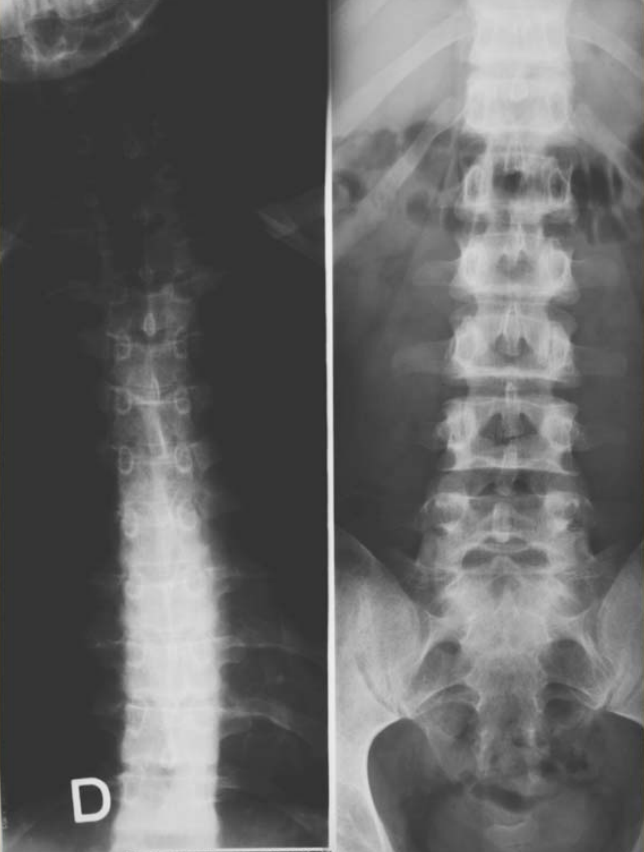

Figure3